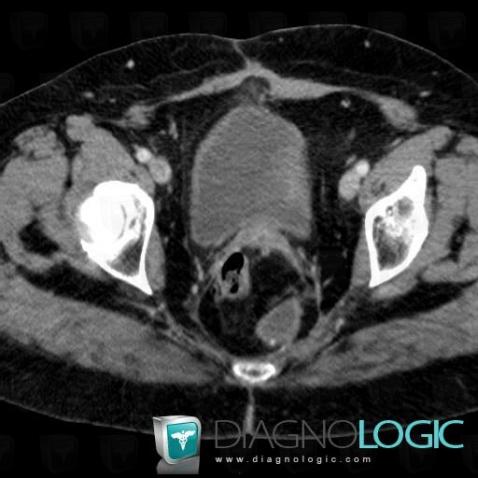

- Diagnosis Abscess, Location(s) Rectum, with gamuts Presacral mass